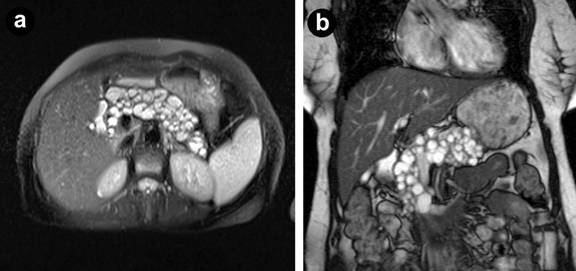

Magnetic resonance cholangiopancreatography (MRCP) was performed with no evidence of cyst communication with the pancreatic duct and no evidence of solid nodules (Figure 1). Endoscopic ultrasound performed showed similar findings with a zero CEA level on aspiration and an amylase level of 365 IU/L. Mucin could not be demonstrated in the aspirate. Given the findings of enlarging cysts, recent diagnoses of diabetes, with the risk of concurrent pancreatic malignancy the patient was offered a total pancreatectomy.

Figure 1. Magnetic resonance cholangiopancreatography demonstrating diffuse cystic lesions throughout the pancreas in transverse (a.) and coronal sections (b.). No clear communication with the pancreatic duct or pancreatic duct dilatation is noted. |